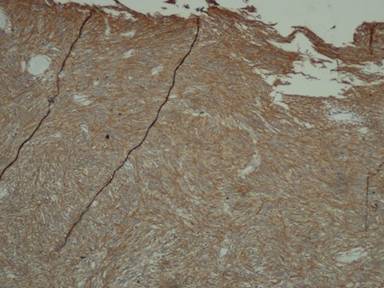

A thirty-year-old man presented with the chief complaint of mass in the right upper abdomen since one and half year. It was gradually increasing in size and was associated with occasional upper abdominal pain. Pain was dull in nature, non-radiating with no specific aggravating and relieving factor. There was history of incomplete bowel evacuation sensation and increased frequency of defecation. There was no history of vomiting, gastrointestinal bleed, jaundice, anorexia and weight loss. On physical examination, there was no pallor, jaundice and lymphadenopathy. A large firm mass about 15x10 cm extending into epigastrium, umbilical and right hypochondrium on per abdomen examination. It had round shape, bosselated surface, smooth margins, and was mobile in the transverse direction. There was no abnormality on digital rectal examination and proctoscopy. Routine laboratory tests were within normal limits. Ultrasound abdomen showed 15x10 cm heterogeneous mass in the umbilical region displacing the adjoining gut loops with no invasion. CECT abdomen showed 15x10 cm size, well defined mass with heterogeneous density in the retroperitoneum extending from pancreas to pelvic brim. It had enhancing peripheral component and non-enhancing (necrotic) central component (Figure 1). Fine needle aspiration cytology of mass smear showed blood only. On exploratory laparotomy there was large hyper vascular mass protruding through the transverse colon mesentery. Mass appeared to be originating from the anterior surface of head of pancreas. It was attached to the whole length of anterior surface of pancreas and macroscopically was not attached with the duodenum except for about one or two cm near the lower end of second part of duodenum (Figure 2). There was no metastasis in liver or peritoneum. Pancreaticoduodenectomy was done. Histopathology showed spindle cell tumor with palisading pattern and foci of necrosis (Figure 3). The mitotic count was up to 15/50 HPF. Tumor was involving duodenal muscularis propria with no infiltration in the duodenal epithelial layer and the pancreas (Figure 4). Immunohistochemical study revealed positive staining for CD117, CD34, vimentin, smooth muscle actin, and negative staining for desmin and CD31 (Figure 5). Based on these findings, the tumor was finally diagnosed as gastrointestinal stromal tumor (GIST) arising from the duodenal wall, growing exophytically and attached with the pancreas without infiltrating the pancreas. Post-operatively patient had biliary leak which was managed conservatively and discharged in satisfactory condition with the advice to take imatinib 400 mg daily.

Figure 4. Histopathology showing tumor involving the duodenal wall (H&E stain, 40x).

Figure 5. Immunohistochemistry showing positivity for CD117 (200x). |